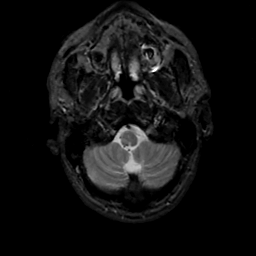

MR Study #12, May 12, 1991 -- Slice #5